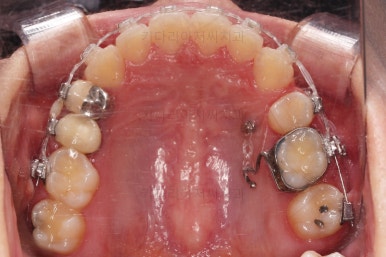

디테일을 좀 더 맞추고 부산치아교정 마무리를 합니다.

치아 갯수 및 사이즈 문제로 위아래의 정중선은 100% 일치시키긴 힘들지만 가능한 선에서 최대한 맞추었고요.

윗니가 1개 없는 상태에서의 교합도 잘 맞추고 마무리를 했습니다.

다시 틈새가 벌어지지 말라고 유지철사를 붙여주었고요.

물론 약간 다시 벌어질 수는 있으나 그 정도는 처음에 비하면 아무 문제도 아닌 정도죠.

전후 비교해 볼게요.

임플란트 하러 오신 분을 임플란트 없이 마무리 했고요.

젊으신 나이에 임플란트를 하기 보다는 약간의 시간을 더 투자해서 이렇게 마무리를 하는게 여러모로 합리적인 치료였습니다.

환자분이나 부산치아교정도 만족스러운 치료였습니다.